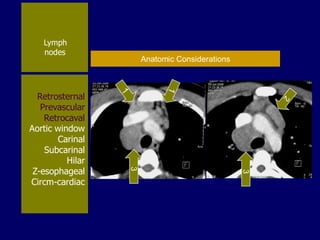

Lymph

nodes

Retrosternal

Prevascular

Retrocaval

Aortic window

Carinal

Subcarinal

Hilar

Z-esophageal

Circm-cardiac